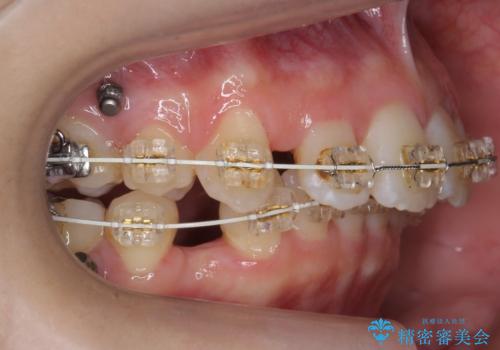

矯正治療をおすすめし、ちょうど虫歯がひどい歯は抜歯して前歯を下げました。

下顎の大臼歯が前に倒れこんでいたため、矯正用ミニスクリューで後ろに起こしています。